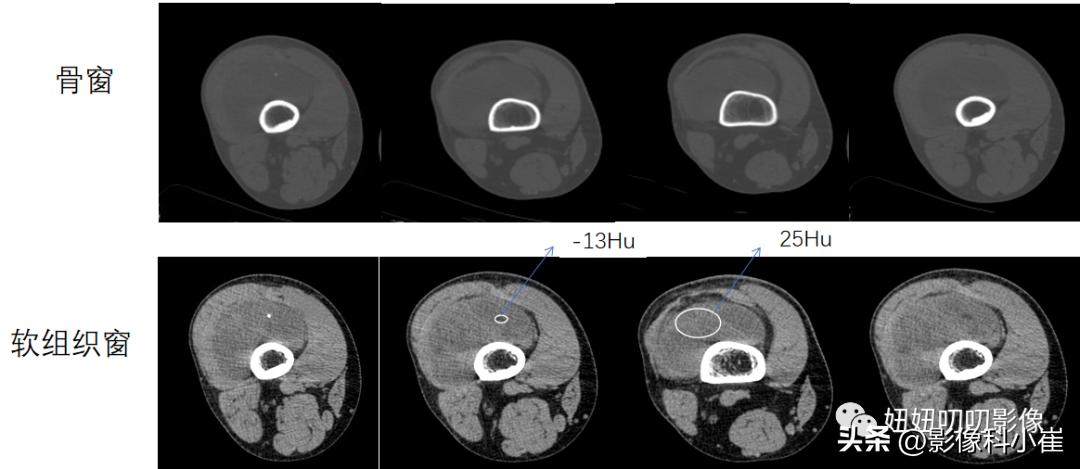

右侧大腿外侧肌肉深部及周围肌间隙可见短长 T1 短长T2 信号,截面范围约12X7X3.5a,T2-FS 局部呈低信号,其余部分呈不均匀高信号,内可见分隔,DWI呈局部扩散受限。相应皮下软组织亦可见小结节状强化灶。所示骨质未见明显异常信号。

A:不是,CT标着-13HU了,磁共振压脂也有低信号,那还说啥了,T2那个粘液看的呦,那叫一个明显,里面有很多纤维分割,主打的就是粘液脂肪肉瘤。